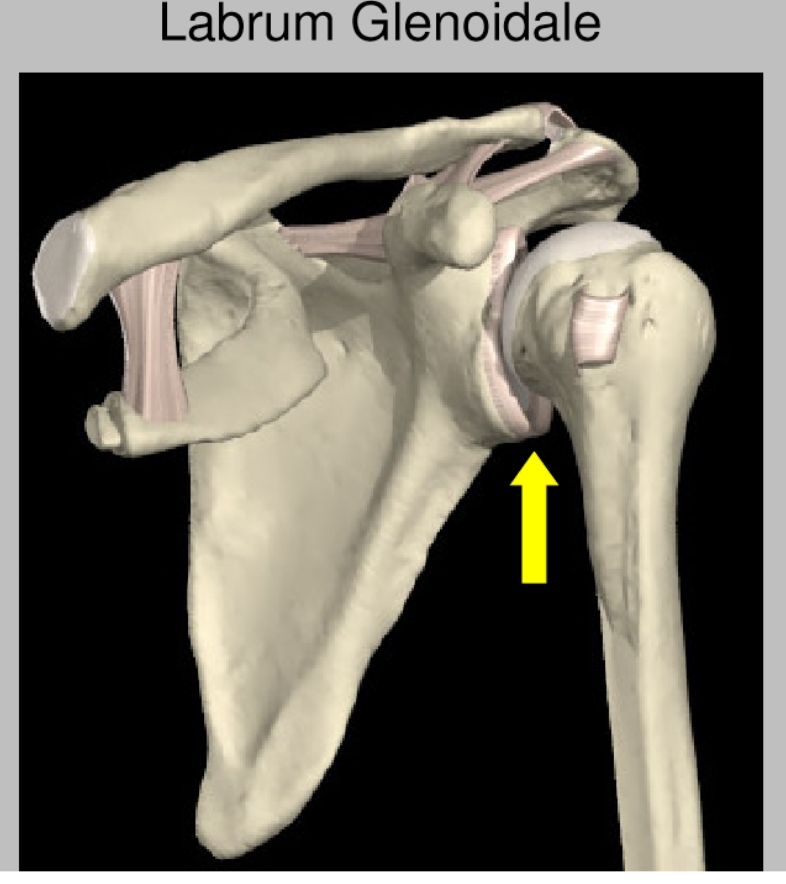

labrum glenoidale

vezelige structuur die de gewrichtspan doet vergroten